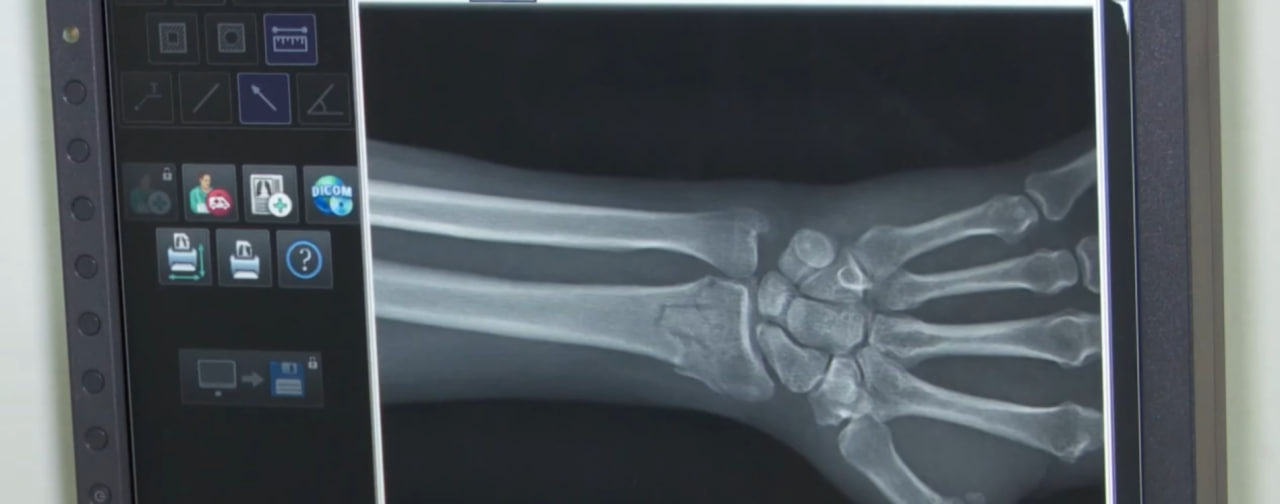

Изображение Здоровье Модернизация и цифровизация. Саратовские больницы и поликлиники получают современное оборудование 11 февраля 2025Поделиться Изменения происходят даже в небольших райцентрах благодаря региональным и федеральным программам.Как это работает? Выясняла Анна Головчинская.Поделиться Эл. адрес Telegram VK OK.ru